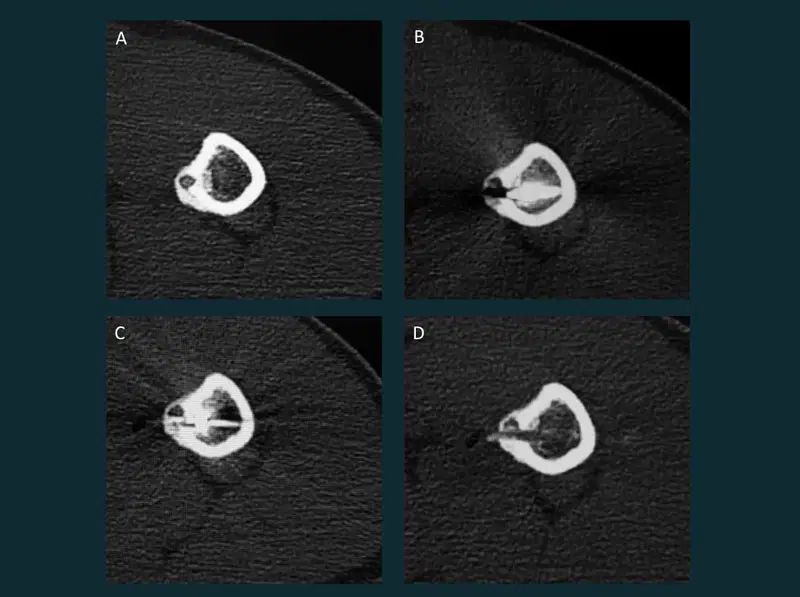

20. Microwave ablation of Osteoid osteoma

Microwave ablation of Osteoid osteoma of the femur IR

Seventeen-year-old boy with pain in the left shoulder for 2 years. Pain is typical of osteoid osteoma which increases at night and is relieved by NSAIDs. A. CT of the left humerus showed an osteoid osteoma in the lesser trochanter. CT guided microwave ablation of the lesion done. Dramatic pain relief observed on the same day. B. Bone drill in place. C. Microwave probe placed in the lesion. D.Post ablation appearance of the lesion with a tiny hemorrhagic spot in the nidus suggestive of ablation changes.